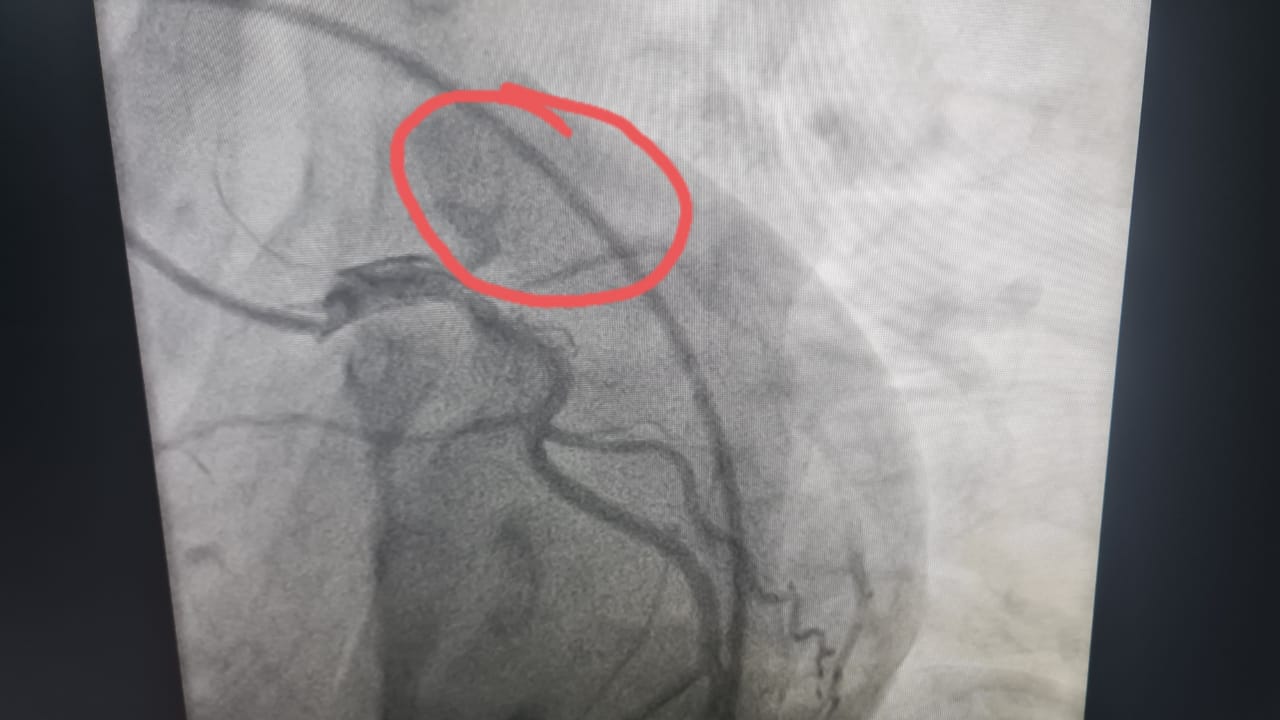

في واقعة طبية نادرة، نجح فريق طبى مساء أمس الأربعاء بوحدة قسطرة القلب بمستشفى طهطا العام  فى إنقاذ حياة شاب يبلغ من العمر 18 عامًا، بعد إصابته بجلطة حادة بالشريان الأمامي الرئيسي للقلب.

وأوضح الدكتور عمرو دويدار، وكيل وزارة الصحة بسوهاج، أن الشاب حضر إلى المستشفى فى حالة حرجة ومتأخرة نسبياً، وبعد إجراء رسم القلب والفحوصات اللازمة تبين وجود جلطة حادة بالشريان الأمامي — وهي من الحالات النادرة جدًا في هذا العمر علي المستوي العالمي.

وأضاف "دويدار" أنه فور الانتهاء من فحص المريض تم العرض علي الفريق الطبي بوحدة قسطرة القلب ، الذى قرر علي الفور إجراء قسطرة قلبية عاجلة لاستكشاف الشرايين التاجية للقلب حيث تبين أن الشريان الأمامي الرئيسي كان مسدودًا بالكامل، وتم فتح الشريان وتركيب دعامة بنجاح تام، واستقرت حالة المريض بعد العملية و يستكمل علاجه بالمستشفى.